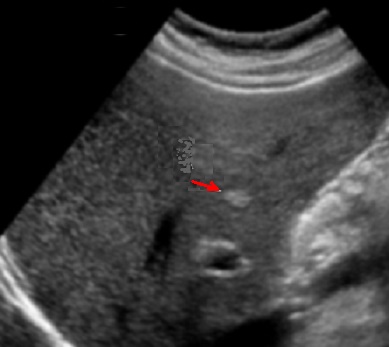

- Image echographique

de kyste simple du foie est :

Aspect lesionel anechogene , homogene ,arrondie ou ovalaire a

renforcement echoriche posterieur . Sa contour est. net , lisse

, peut etre en cloisone et avascularisation

Aspect lesionnel du kyste est arrondie aechogene a

bord tres nette et lisse , situe

a lobe droit du foie . Ombre de hyperascoustique porterieure

du kyste en visualise tres net . Image echographie

percutanee du kyste simple du foie |